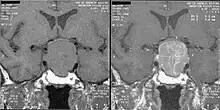

Frequent serum GH measurements in normal subjects (left panel) demonstrate that GH can fluctuate between undetectable levels most of the time interspersed with peaks of up to 30 μg/L (90 mIU/L); in acromegaly (right panel) GH hypersecretion is continuous with no undetectable levels.